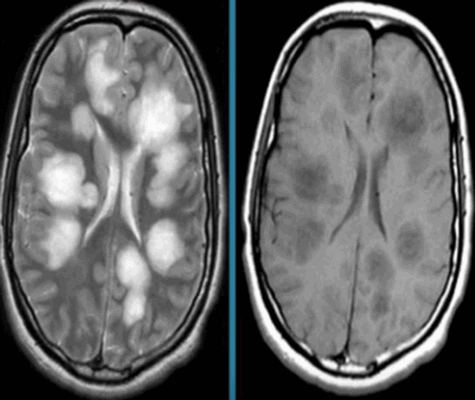

Злокачественные опухоли составляют до 50% всех опухолей головного мозга. Эти опухоли врач определяет по:

- нечеткости и неровности контуров и формы опухоли;

- большому перифокальному отеку;

- наличию “масс-эффекта”;

- неоднородному накоплению контрастного усиления;

- типу накопления контраста.